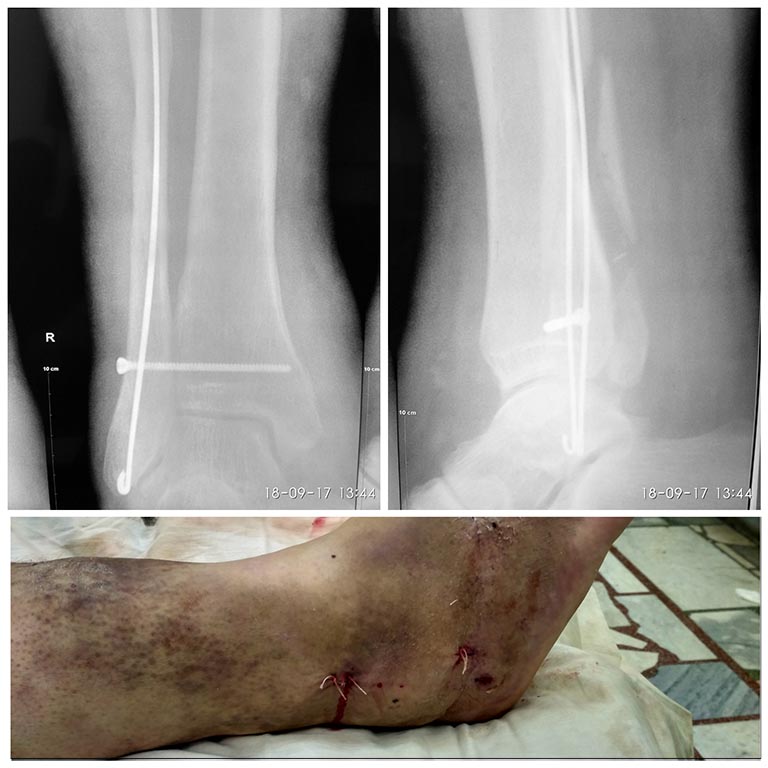

Пациент, 36 лет, сохранный, социально активный, избыточного питаниия. Получил перелом лодыжек. В анамнезе тромбоз глубоких вен голени на этой же конечности, ПТФС, кава-фильтр, на варфарине, нога "скорей мертвая,чем живая)". Как лечить?

Артерии проходимы ,глубокие вены - тромбоз ,возвратный кровоток за счет поверхностных, эластичная компрессия противопоказана.

Учитывая проблемы с мягкими тканями, стоит подумать над малоинвазивными вариантами остеосинтеза.

Например, временный аппарат для восстановления длины малоберцовой и устранения подвывиха стопы, далее закрытая внутрикостная фиксация малоберцовой одной-двуся спицами, чрескожно винт через наружную лодыжку в большеберцовую для фиксации ее длины и межберцового диастаза. Дальше либо оставить на несколько недель в аппарате, либо в задней шине.

Ножка не фонтан, конечно. Вопрос. На фото дата 15.09. Это уже 10 дней однако. А что, вывих стопы не устранён но сих пор? Если да, то что остановило в ургентном порядке устранить вывих стопы, чрезкожно интрамедуллярно в малоберцевую пару спиц Киршнера (если стремно MIPO), задний край большеберцевой опять же чрезкожно винтом или хотя бы спицами, или не трогать, в крайнем случае, и позиционный винт опять же чрезкожно, и задняя лонгета?

Мы этого пациента обсуждали с Максимом Агалаковым несколько дней назад в мессенджере. IMHO все сделали очень красиво. И анатомию восстановили хорошо, и очень щадяще получилось.